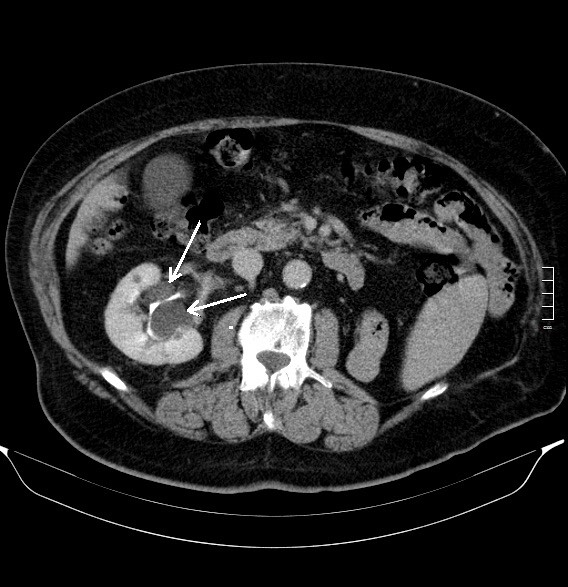

2906. Образования в правой почке, указанные стрелками, являются